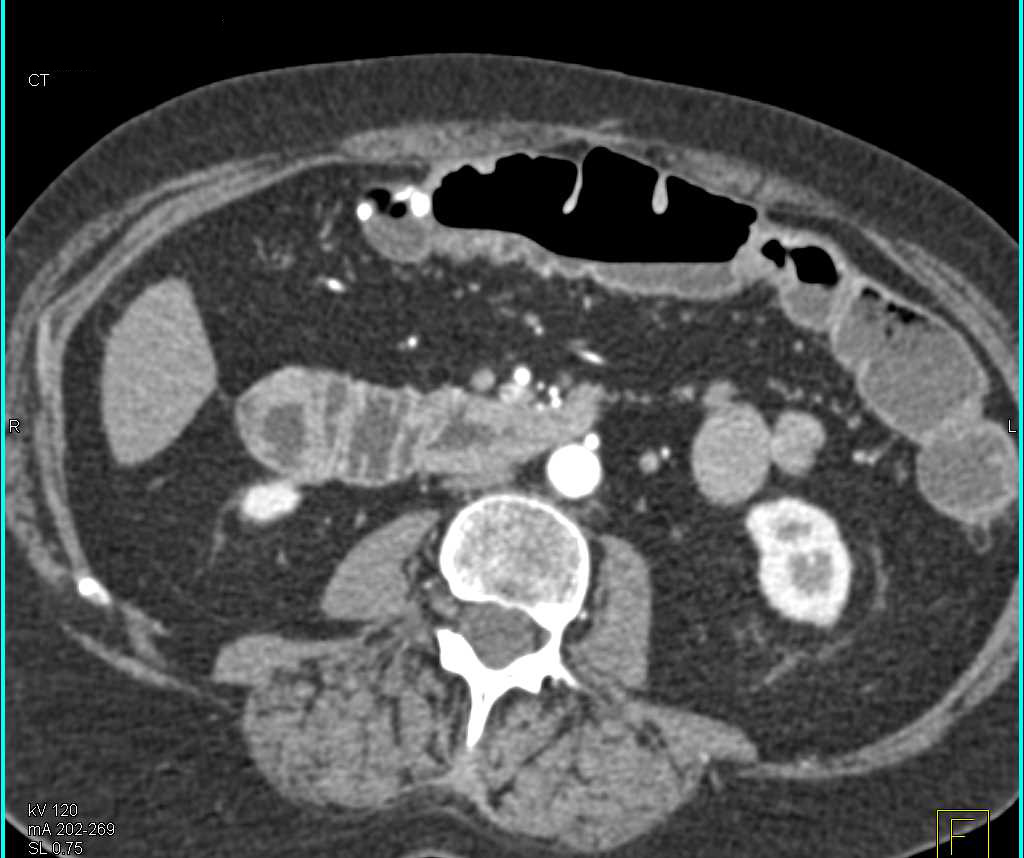

Crohn's Colitis Colon Including the Rectum with CTA